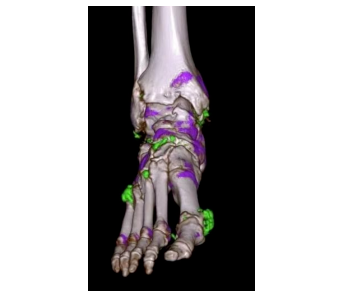

雙能量成像精準(zhǔn)識(shí)別病灶成分,可無創(chuàng)檢查痛風(fēng)

通過高低雙能量掃描,可區(qū)分鈣化、尿酸結(jié)晶、脂肪等成分,精準(zhǔn)定位痛風(fēng)石、腎結(jié)石成分,輔助制定個(gè)性化治療方案。 腫瘤活性分析、心肌缺血評(píng)估等功能,為腫瘤治療隨訪及心血管疾病診療提供分子級(jí)信息。